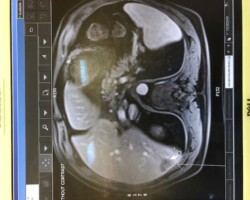

Resection of large retroperitoneal sarcoma including right and transverse colectomy and right hepatectomy